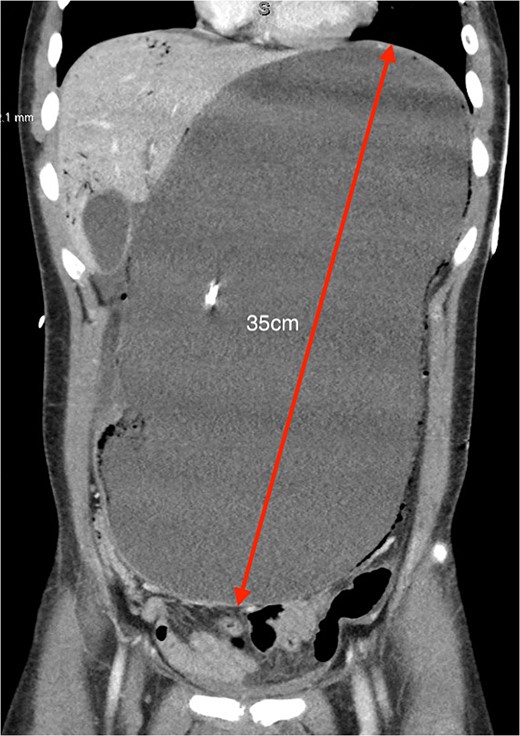

An 18-year-old male presented with severe abdominal pain, distension, and vomiting after a buffet meal. He had a BMI of 22 (weight 71 kg, height 181 cm) and no significant medical history or recent weight loss. He was normotensive (110/80), tachycardic (>120 bpm), and febrile (38.9°C). Examination revealed lethargy, a grossly tympanic, distended and tender abdomen. Biochemical tests showed severe lactic acidosis (pH 7.13, lactate 13.7), leukocytosis (white cell count 21×108) and acute kidney injury (creatinine 203 μmol/L, glomerular filtration rate 40 ml/mn/1.73m2). CT scan revealed acute gastric dilatation (35×19×12 cm), gastric pneumotosis and portal venous gas (Figs 1 and 2) with aortomesenteric angle of 5° and distance of 6 mm (Fig. 3). There were broad differentials considered at the time of presentation including both mechanical and functional aetiologies (Table 1).

Coronal CT showing severely distended stomach to the pelvis (35 cm in greatest length) with evidence of pneumotosis and portal venous gas.